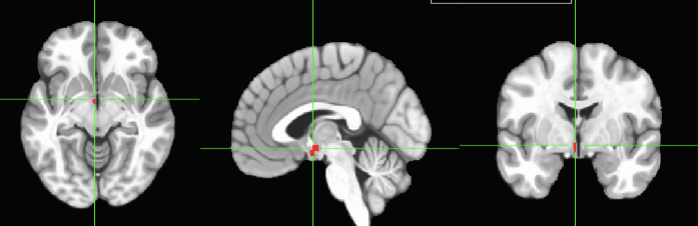

HYPOTHALAMUS– This is the left hemisphere, we have a right

hypothalamus as well. Both, left and right, are important for

motivating behaviors. Remember that it is part of the

diencephalon. We will study more about the hypothalamus

(for example, sleep, eating behavior,…) later in the semester.